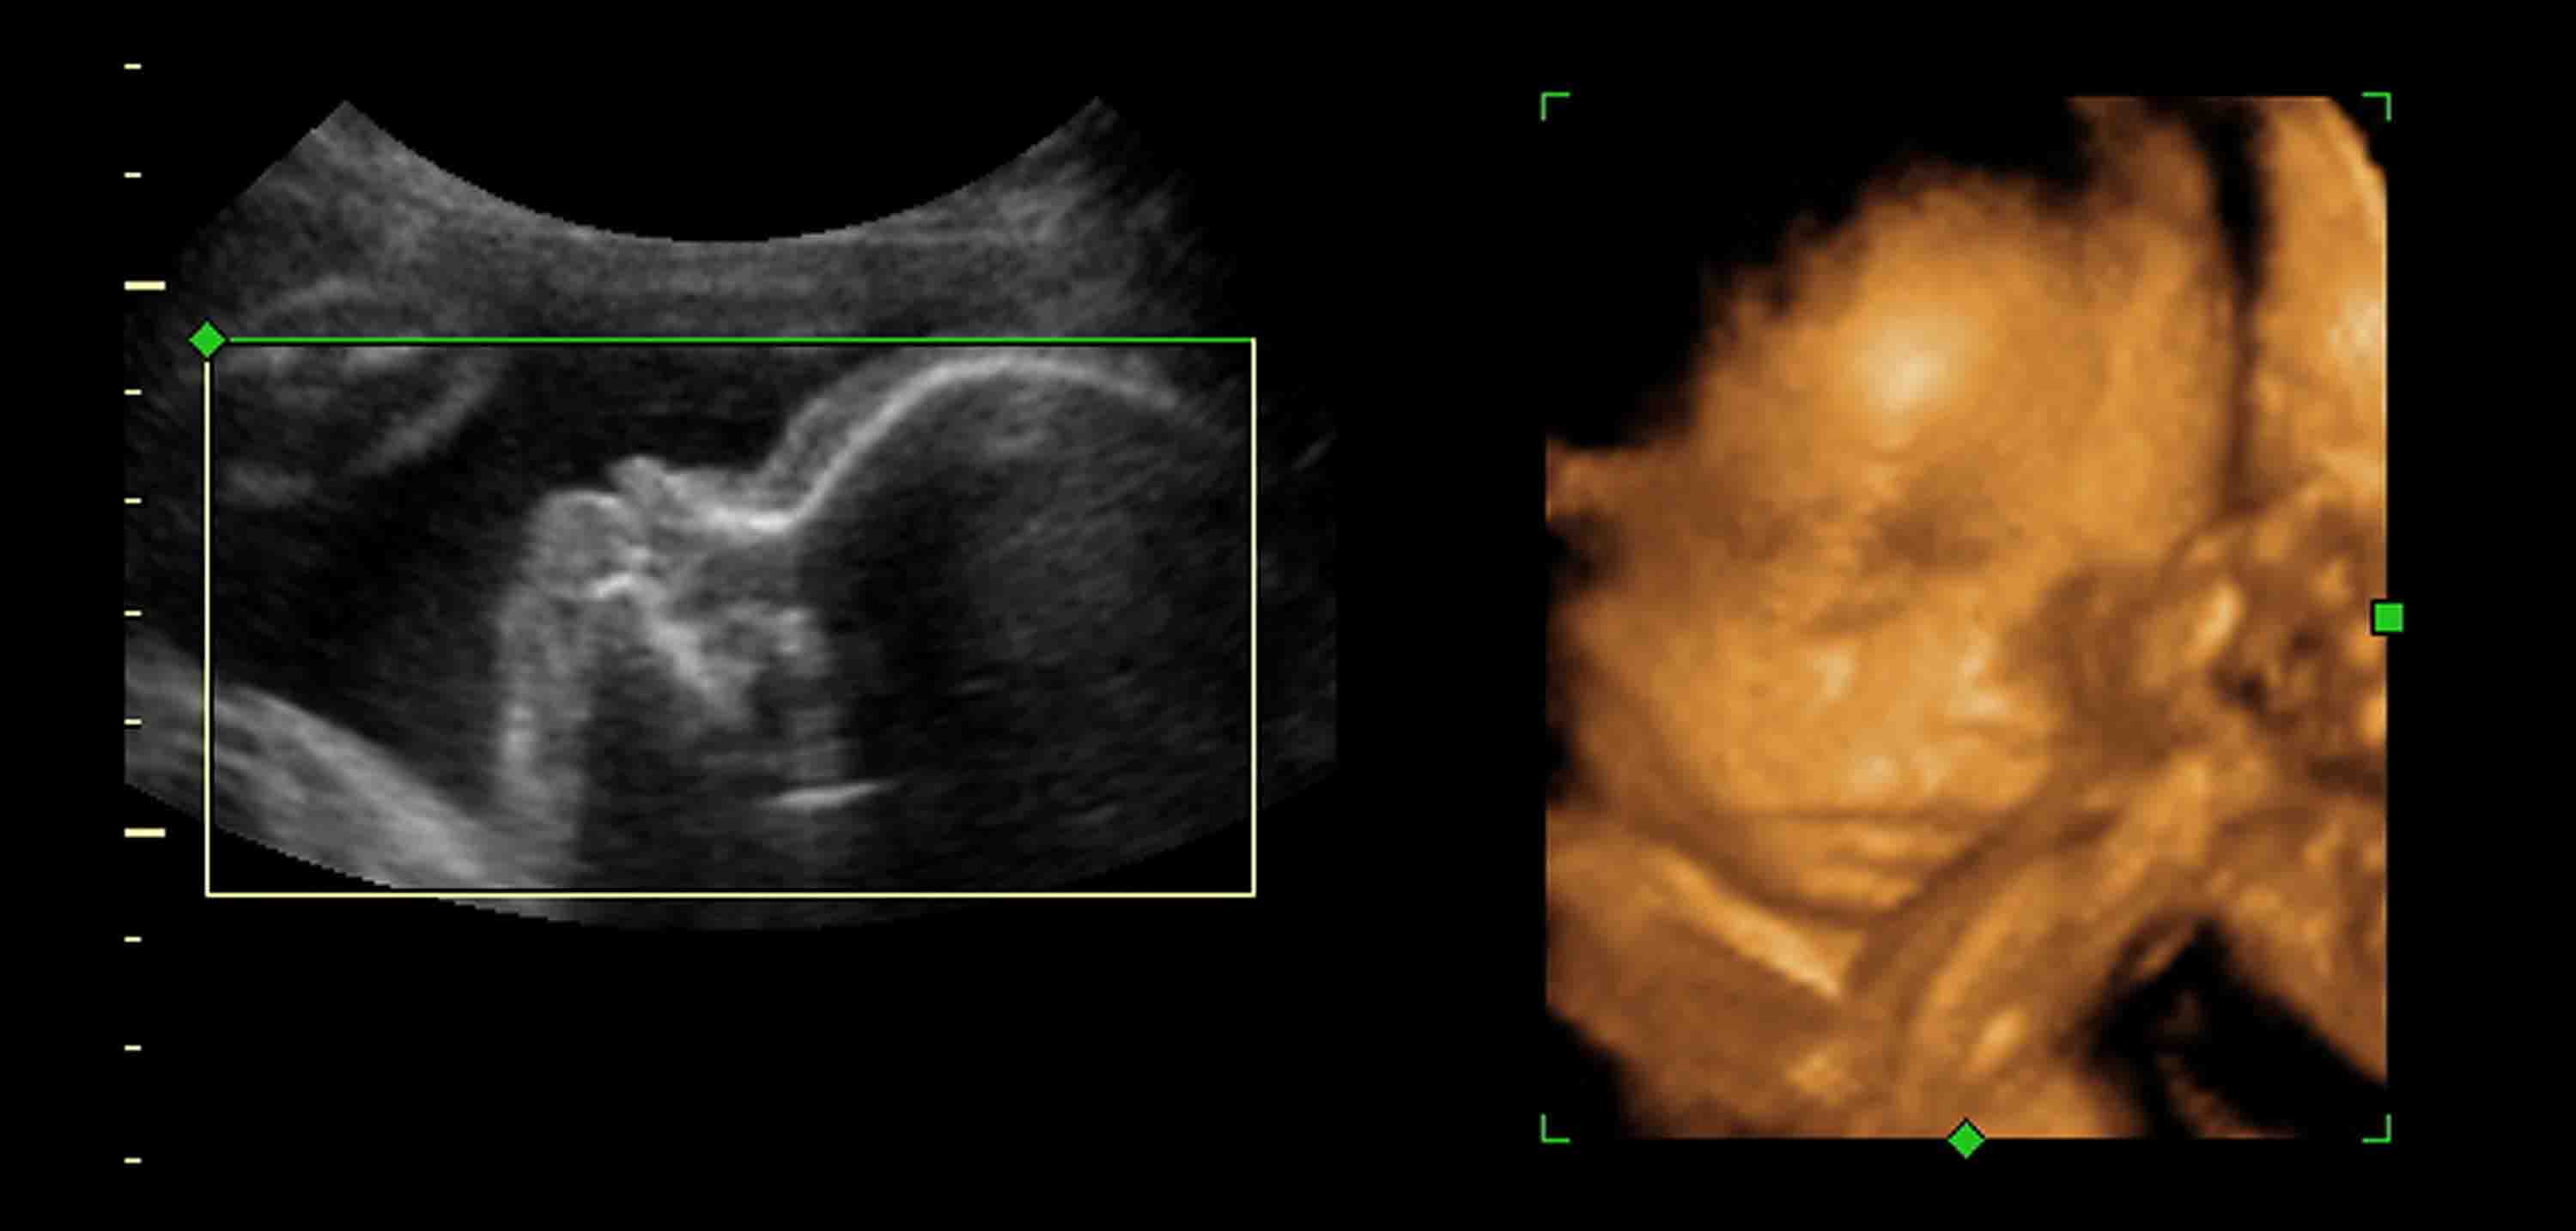

Con las ecografías 3D se toman miles de fotos del bebé para convertirlas en imágenes tridimensionales. Esto permite que se pueda ver al bebé en tres dimensiones en lugar de dos, pudiendo ver profundidad y forma dando claridad a la silueta del bebé. En las ecografías 3D, se hace uso de un software más avanzado y moderno, por lo que hace.. Precios ecografías en Villavicencio | BabyCenter. Colombia - Mamás y embarazadas colombianas .